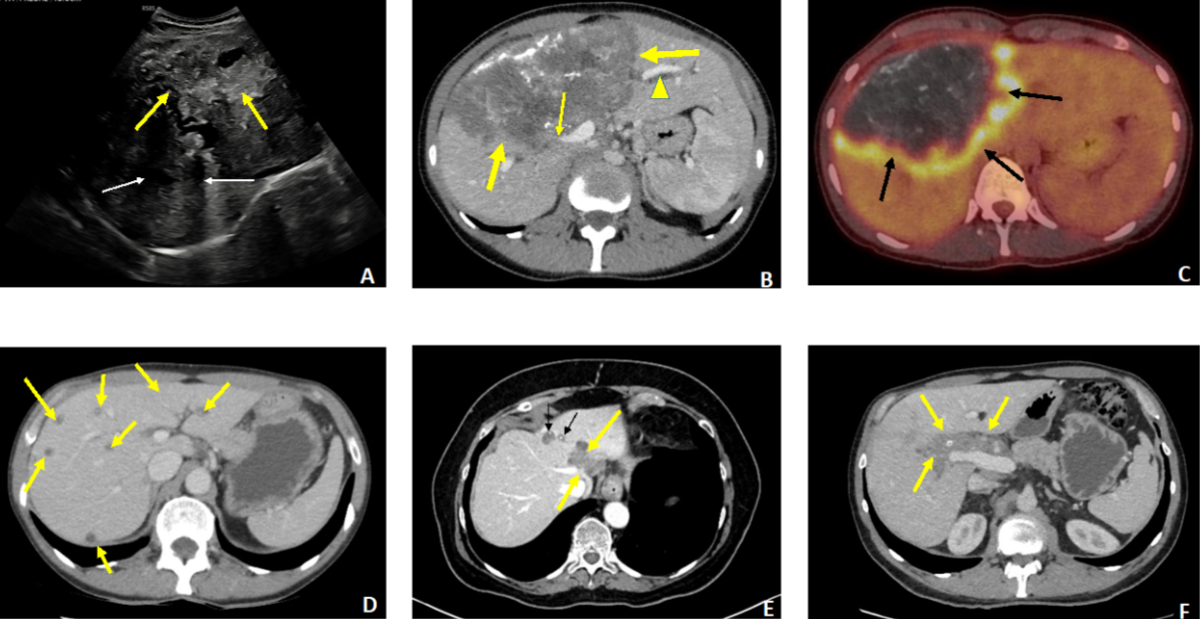

Figure 4A–C: 27-year-old female patient revealing advanced hepatic alveolar echinococcosis (AE) with cholestatic jaundice. A: Ultrasound: extensive heterogeneous lesion of the right lobe with irregular contours (thick arrows), containing numerous calcifications with posterior shadow cones (thin arrows). B: Contrast-enhanced CT scan, portal phase, axial section. The huge lesion (thick arrows) involves segments IV, V, VI and VIII with invasion of the right portal branch (thin arrow) and the hilum, causing dilation of the intrahepatic bile ducts in the non-infected left liver (arrowhead). C: PET-CT, axial section. Intense perilesional activity (arrows). D–F: Three cases of AE diagnosed at a pauci- or asymptomatic stage. D: 56-year-old patient, abdominal discomfort. Contrast-enhanced CT scan, portal phase, axial cut. Multiple small scattered AE foci in both lobes, without calcified components. E: 66-year-old patient, renal transplant recipient. Incidental discovery (imaging for sigmoiditis) of hepatic AE. Contrast-enhanced CT scan, arterial phase, axial section. Two foci located in segment IV. Only the anterior focus contains punctate calcifications (thin arrows). The posterior focus invades the left and median suprahepatic veins (thick arrows). F: 45-year-old patient. Discovery of AE during an annual routine blood test showing a slight elevation of gamma-GT. Contrast-enhanced CT scan, portal phase, axial section. Centrohepatic lesion with a low calcified component, hilar and pedicular infiltration and invasion of the hepatic artery (arrows).

Nearly half of the patients were asymptomatic at the time of diagnosis, aligning with observations from recent European series [15, 19]. In France, the proportion of asymptomatic patients increased from 24% (1982–1992) to 50.2% (2003–2013), and for the latest years (2014–2018), asymptomatic forms (60.4%) became clearly more frequent than symptomatic forms [19]. In a German series published in 2017, 44% of patients were asymptomatic at diagnosis for the period 2000–2011, compared to 21.3% for the earlier period, 1992–1999 [15]. In our study, jaundice, a classic inaugural symptom of alveolar echinococcosis and a sign of advanced disease, was present in only 4 cases. The most frequent revealing symptom was abdominal pain (53% of cases), leading to imaging studies. Due to the earlier diagnoses during the course of alveolar echinococcosis, low PNM stage (I or II) was reported in nearly 50% of the patients, which is in accordance with recent data reported in Germany [15]. Among these asymptomatic forms, we noted a particular pattern in 3 patients that has been little described to date: multiple small, minimally or non-calcified nodules scattered in the hepatic parenchyma (figure 4D). This could represent an early stage of alveolar echinococcosis, preceding the more typical appearance resulting from the confluence of these lesions, associated with the progressive development of the calcified component [19]. Interestingly, for these 3 patients, the therapeutic orientation was long-term albendazole treatment due to the multifocal nature of alveolar echinococcosis, with a fairly rapid observation of an objective response. This allowed, in one case, an attempt to stop treatment after 3 years.